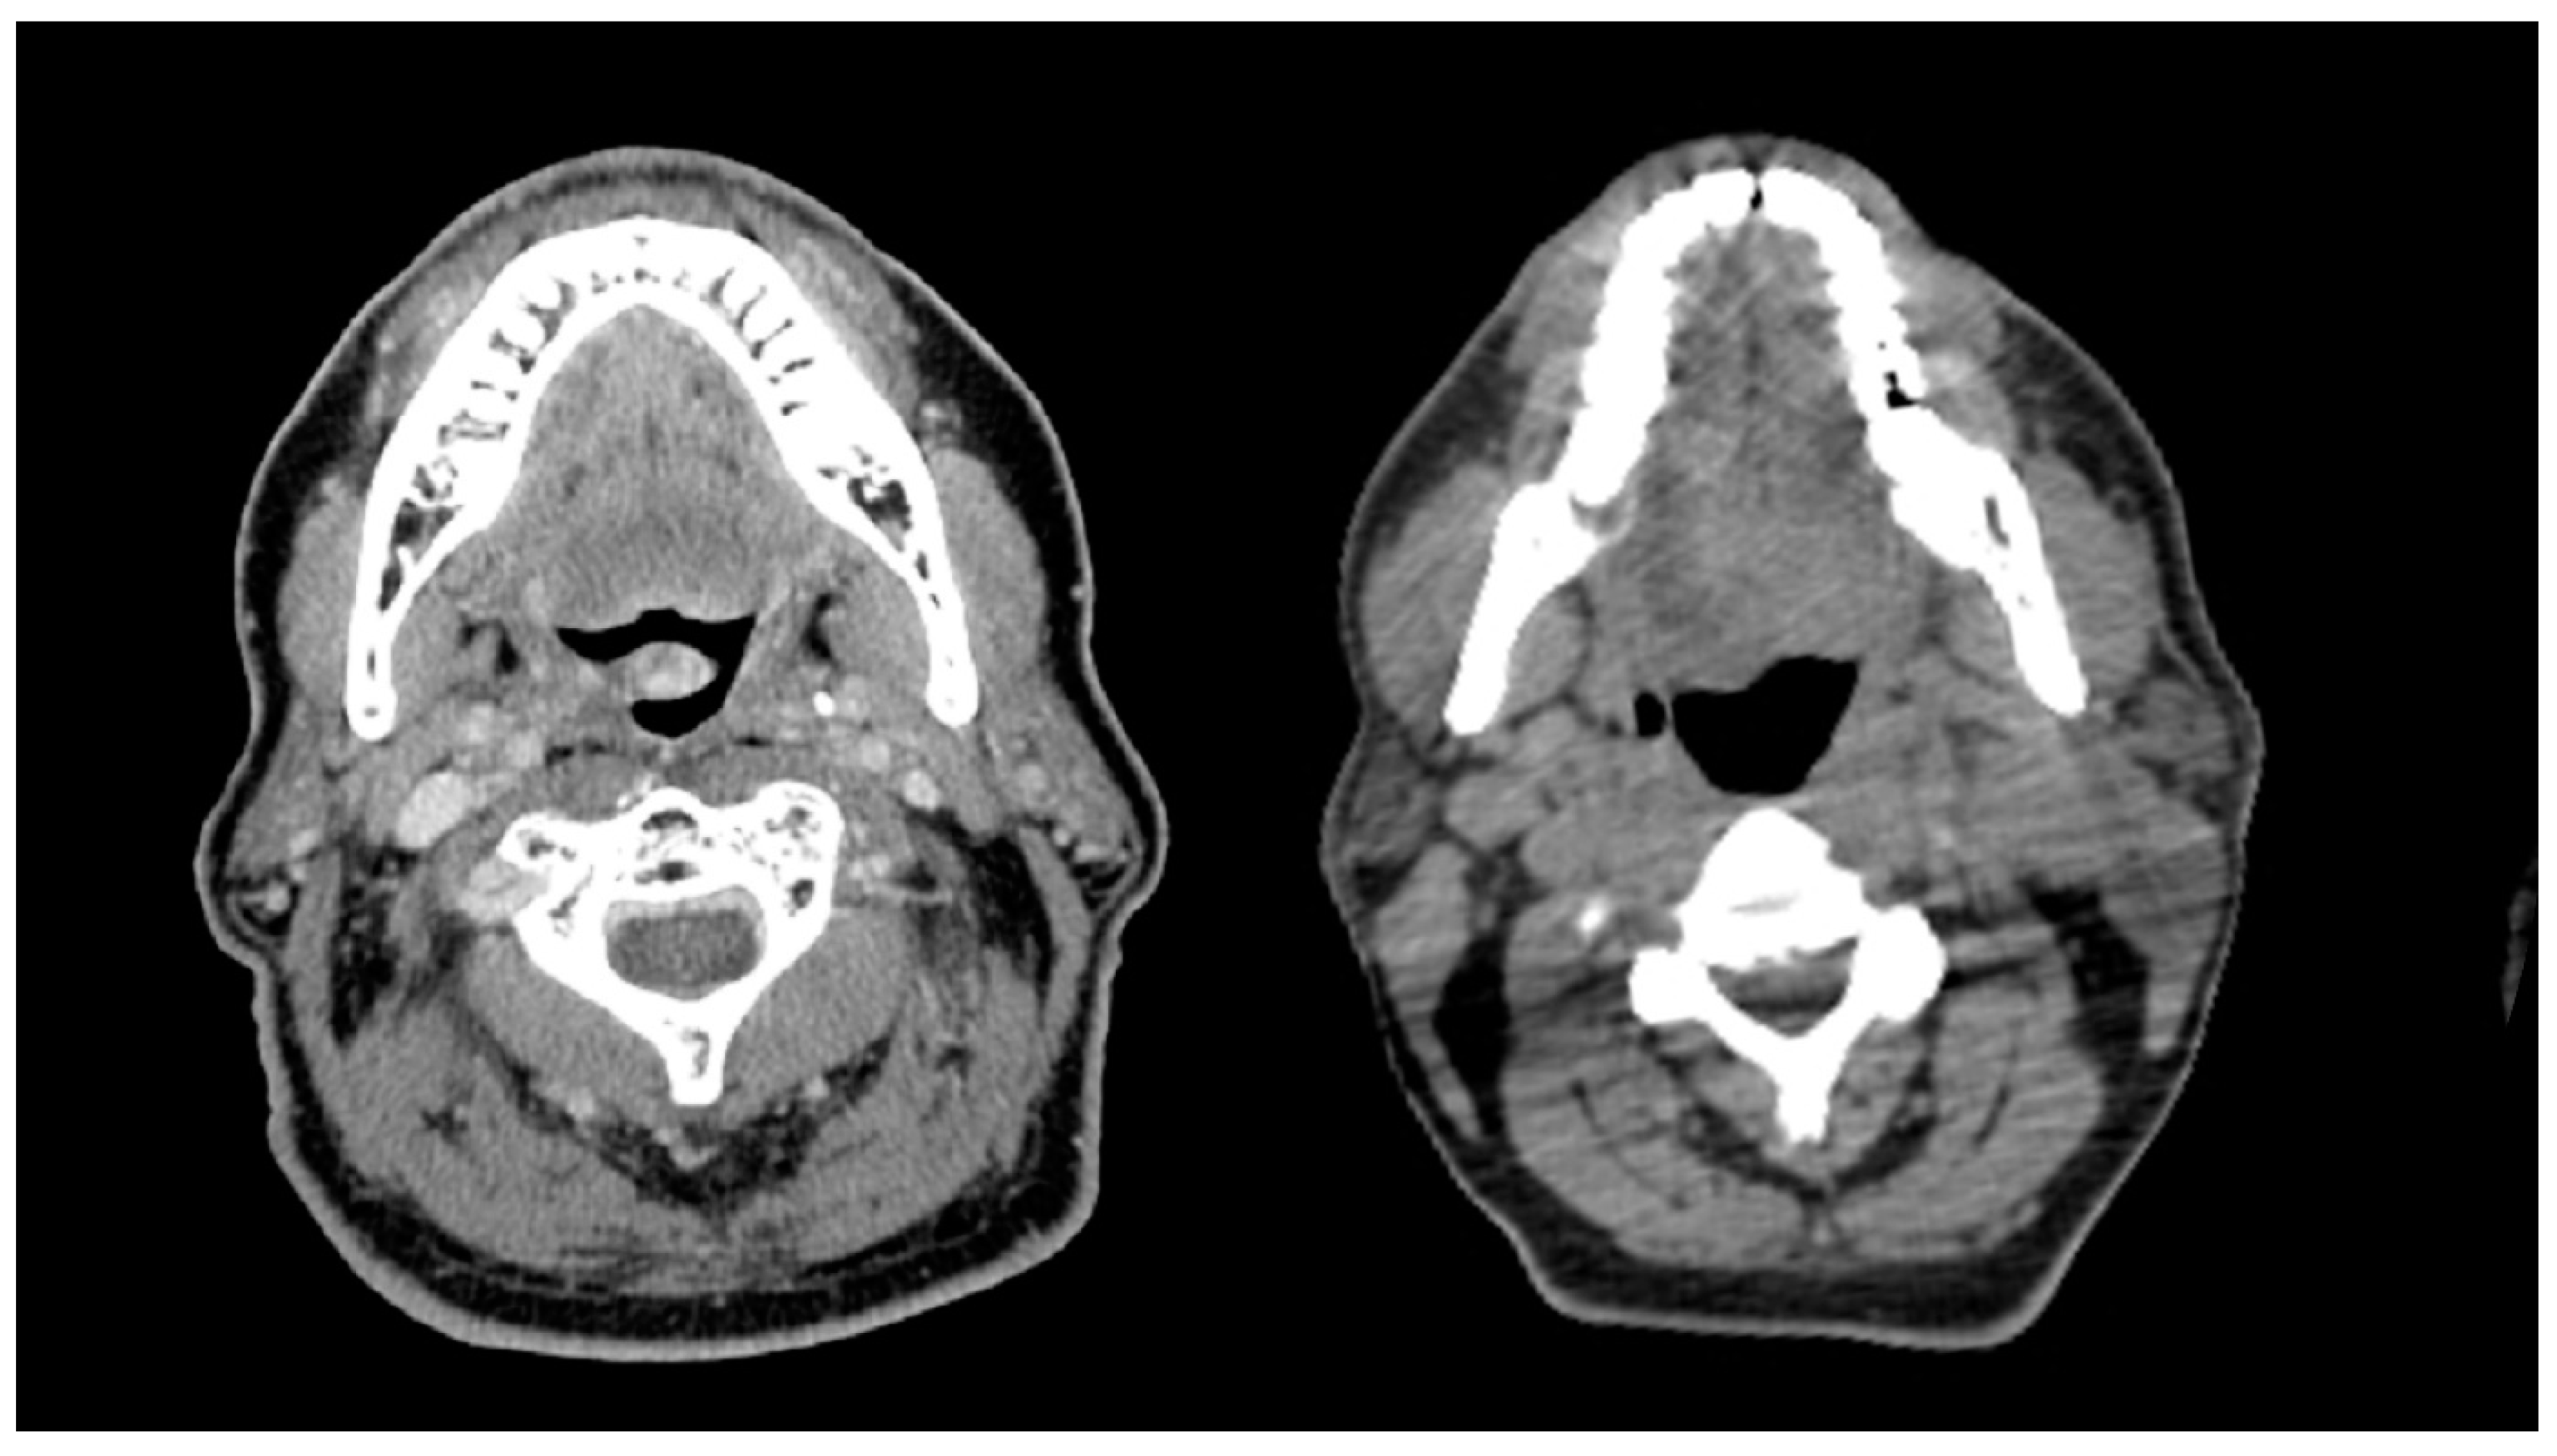

2.3. Body Composition Measurement

- Gomez-Perez, S.L.; Haus, J.M.; Sheean, P.; Patel, B.; Mar, W.; Chaudhry, V.; McKeever, L.; Braunschweig, C. Measuring Abdominal Circumference and Skeletal Muscle From a Single Cross-Sectional Computed Tomography Image: A Step-by-Step Guide for Clinicians Using National Institutes of Health ImageJ. J. Parenter. Enter. Nutr. 2015, 40, 308–318. [Google Scholar] [CrossRef] [Green Version]

- Swartz, J.E.; Pothen, A.J.; Wegner, I.; Smid, E.J.; Swart, K.M.; de Bree, R.; Leenen, L.P.; Grolman, W. Feasibility of using head and neck CT imaging to assess skeletal muscle mass in head and neck cancer patients. Oral Oncol. 2016, 62, 28–33. [Google Scholar] [CrossRef]